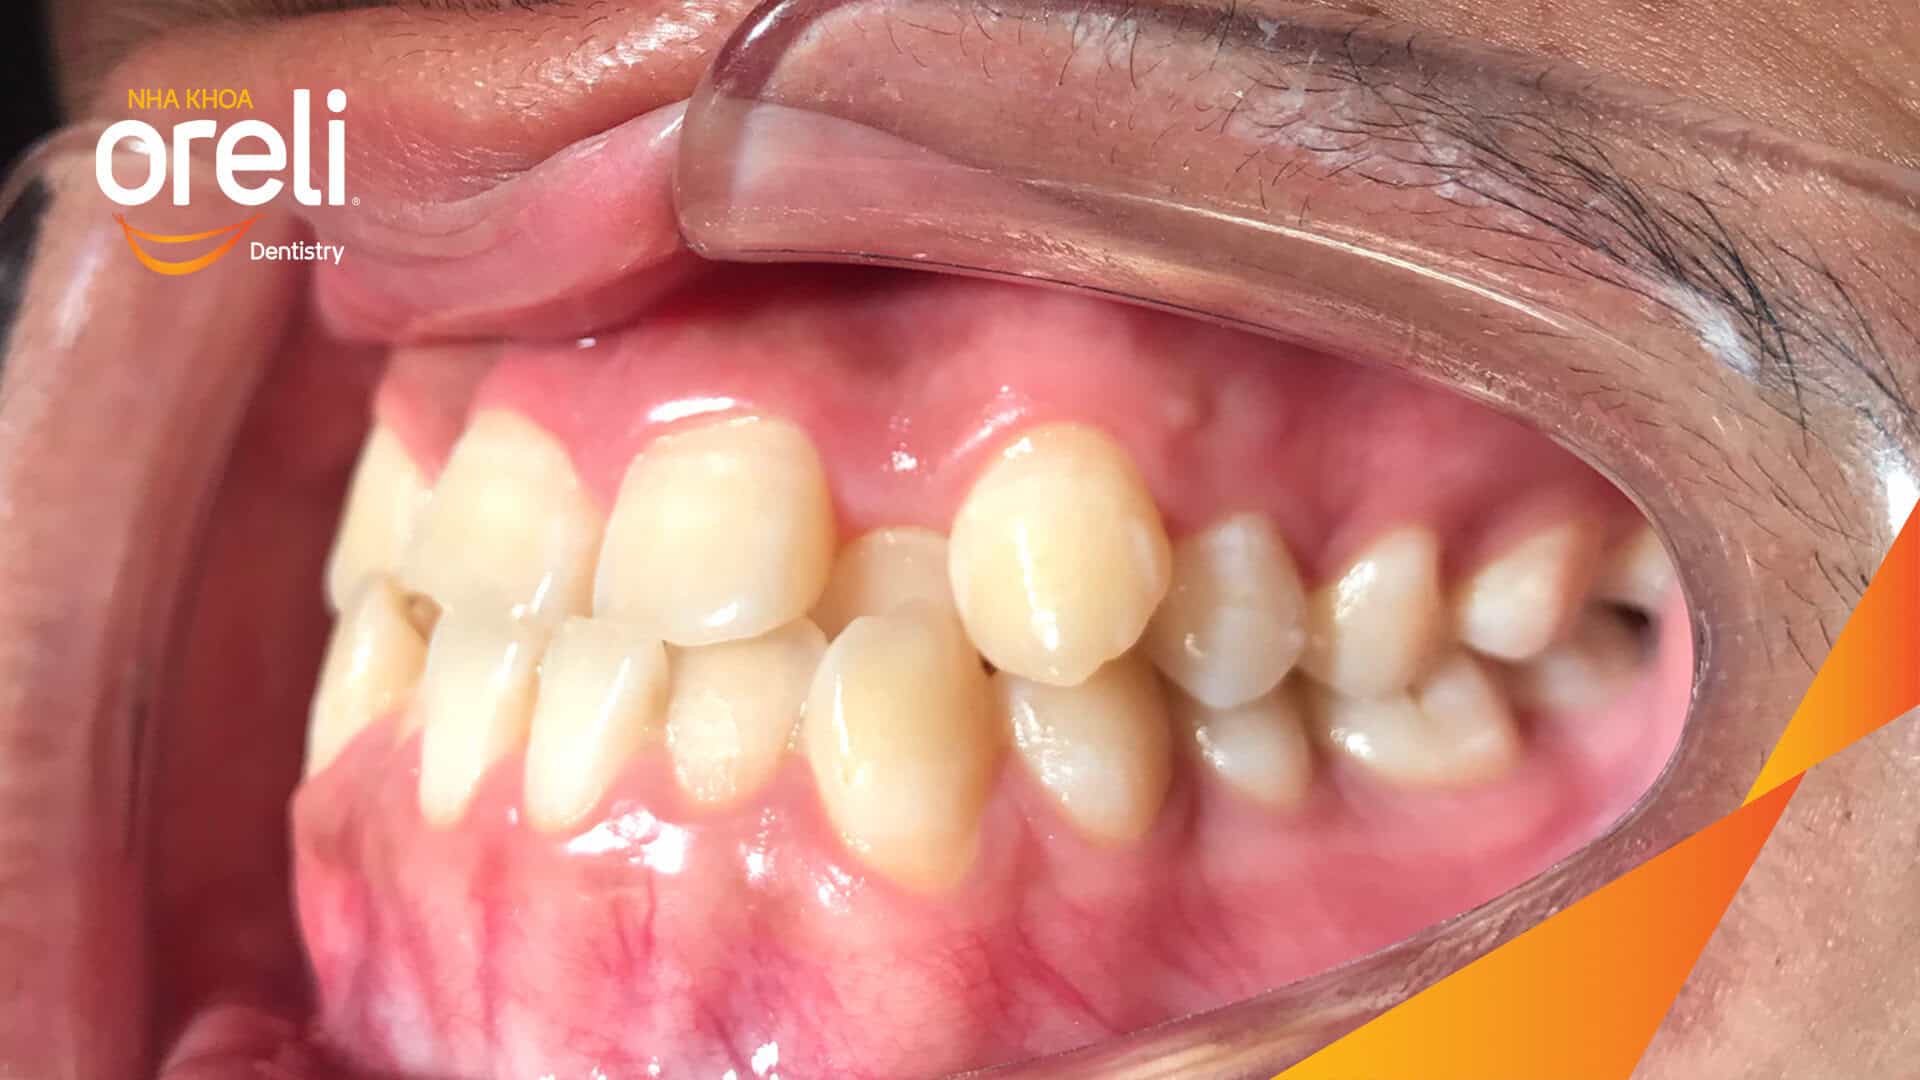

Ca niềng chỉnh chen chúc hẹp hàm nặng cả trên và dưới – Kết quả điều trị thực tế tại nha khoa Oreli Niềng răngChen chúc Xem thêm